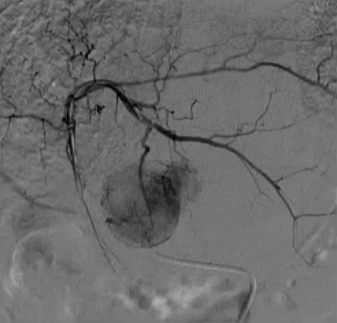

血管造影发现腹腔干狭窄,通过肠系膜上动脉侧支建立通路(图二)。

微导管精准置入肝动脉,缓慢输注顺铂(75mg/m²)及吉西他滨(1000mg/m²),联合DSM微球栓塞(图三)。